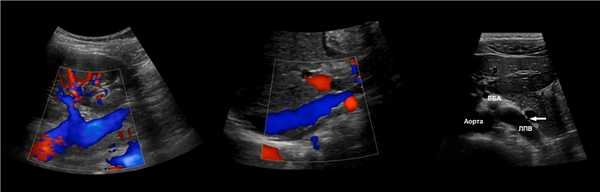

ППА проходит позади нижней полой вены. ЛПВ проходит через «пинцет» между аортой и верхней брыжеечной артерией. Иногда встречается кольцевидная ЛПВ, тогда одна ветвь располагается впереди, а другая — позади аорты.

Рисунок. Почечные вены впадают в нижнюю полую вену (1, 2). Аортомезентериальный «пинцет» может сдавливать ЛПВ (3).